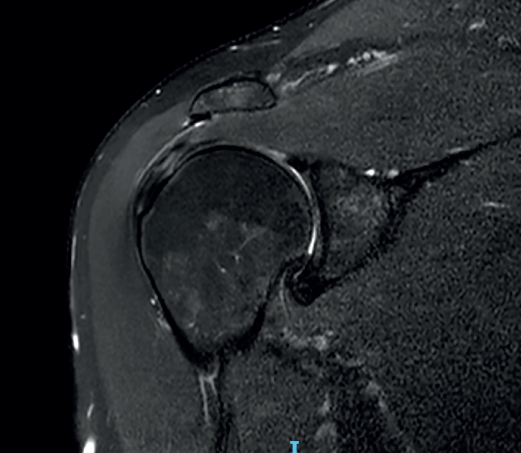

Figure 6. Severe supraspinatus tendinopathy in T2-weighted imaging.

The characteristic MRI image of tendinosis consists of a focal or intra-substance zone of intermediate signal intensity in T1-weighted imaging which does not disappear in T2 sequencing and does not reach fluid signal intensity in T2-weighted imaging (Figure 6). We can sometimes observe diffuse or focal thickening of the tendon, without evidence of rupture(33). Tendinosis may prove difficult to distinguish from early-stage partial rupture of the tendon.